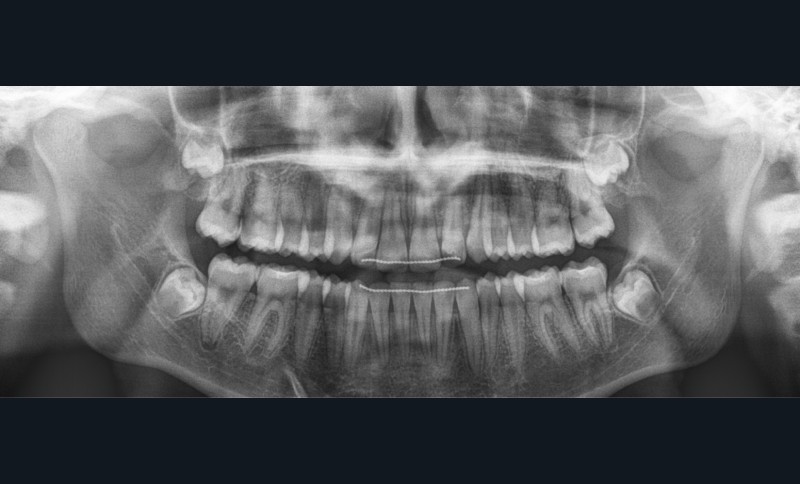

Sur la radiographie panoramique, on observe une transposition des canines maxillaires en place d’incisives latérales, au contact des racines de 11 et 21.

À ce stade, une radiographie panoramique est réalisée pour s’assurer de l’intégrité des racines, contrôler les axes dentaires et planifier le repositionnement de certaines attaches ainsi que le collage des tubes sur les secondes molaires en cours d’éruption.